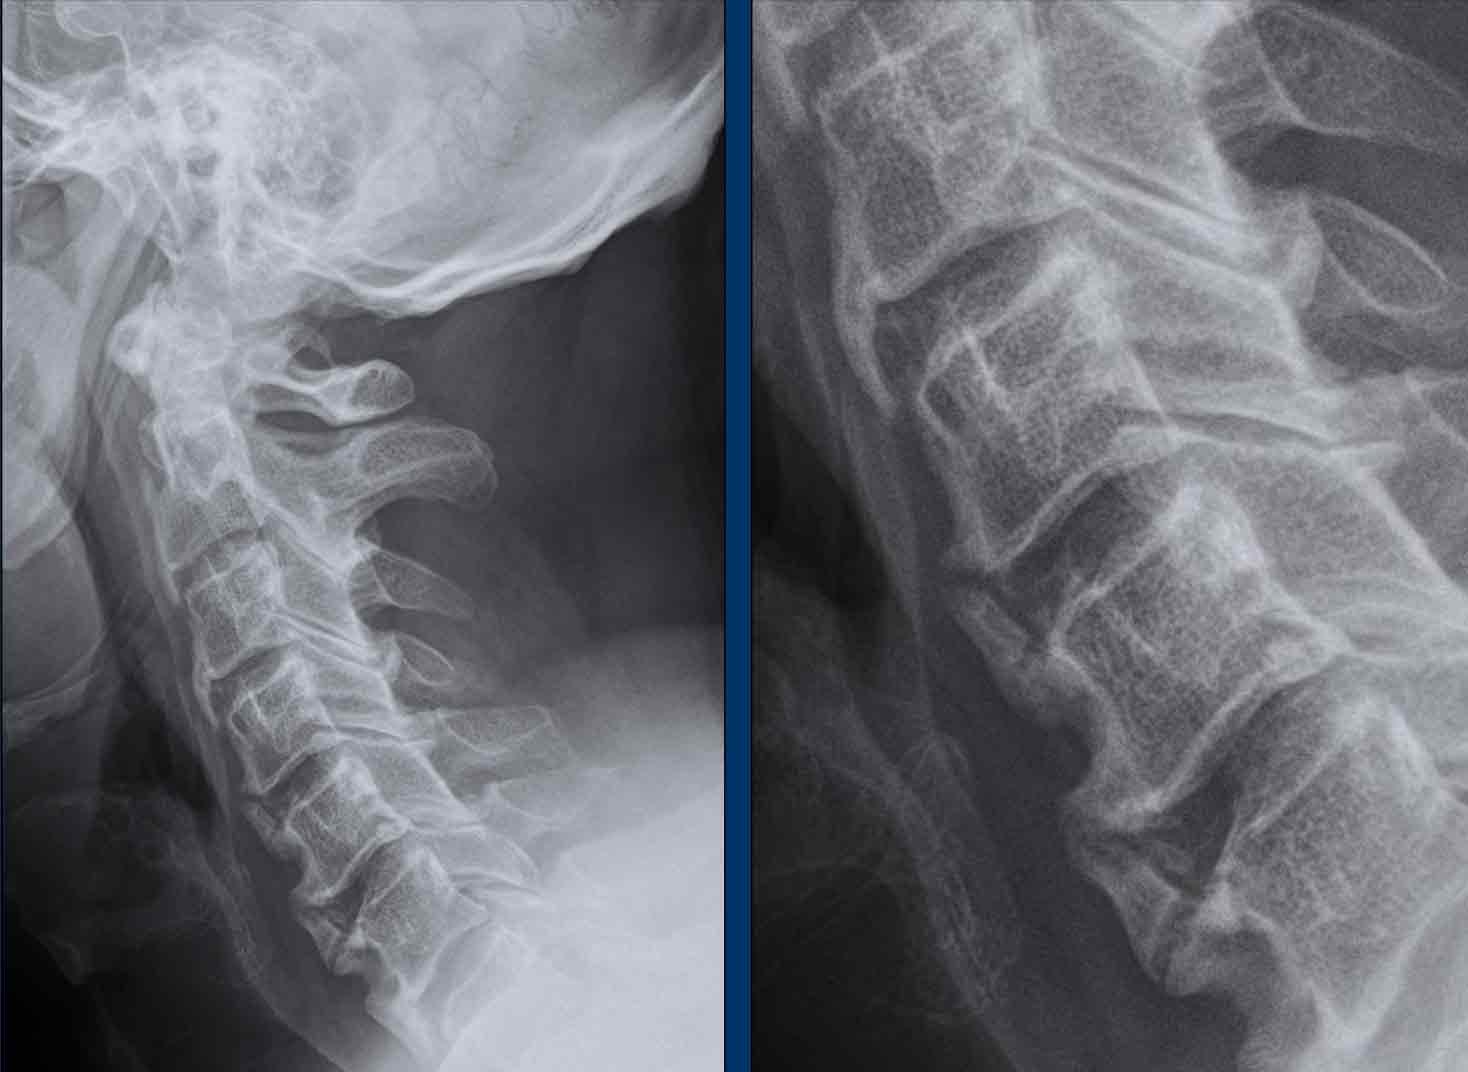

Trật khớp đội – trục

Cột sống cổ thường bị ảnh hưởng trong viêm khớp dạng thấp và có thể biểu hiện dưới dạng mất vững khớp đội – trục, trật khớp dưới trục hoặc lồng nền sọ kèm theo sụt lún sọ não.

Sụt lún sọ não xảy ra khi mỏm răng xâm lấn vào lỗ chẩm.

Trật khớp đội – trục là một biến chứng quan trọng và có thể đe dọa tính mạng của viêm khớp dạng thấp. Tình trạng này được xác định khi khoảng cách giữa mỏm răng C2 và cung đốt đội vượt quá 3 mm. Nguyên nhân là do lỏng lẻo dây chằng do viêm.

Mất vững tại khớp này có thể gây ra nhiều triệu chứng thần kinh do chèn ép tủy sống.

Hình ảnh

Khi cúi cổ, khoảng cách giữa mỏm răng và mặt sau cung trước đốt đội bị giãn rộng (14 mm) (bình thường ≤3 mm).

Lồng nền sọ

Lồng nền sọ, còn gọi là sụt lún sọ não hay ấn nền sọ, xảy ra ở 5-10% bệnh nhân viêm khớp dạng thấp cột sống cổ.

Trong lồng nền sọ, mỏm răng sa vào lỗ chẩm làm thu hẹp không gian dành cho tủy sống.

Biểu hiện lâm sàng đa dạng, từ đau đầu mạn tính, hạn chế vận động cổ đến suy giảm thần kinh cấp tính (chèn ép tủy sống và thân não, có thể dẫn đến liệt hoặc thậm chí tử vong nếu cổ bị di chuyển ở một số tư thế nhất định).

Cuộn xem các lát cắt CT.

Có hình ảnh di chuyển lên trên của mỏm răng vào lỗ chẩm.